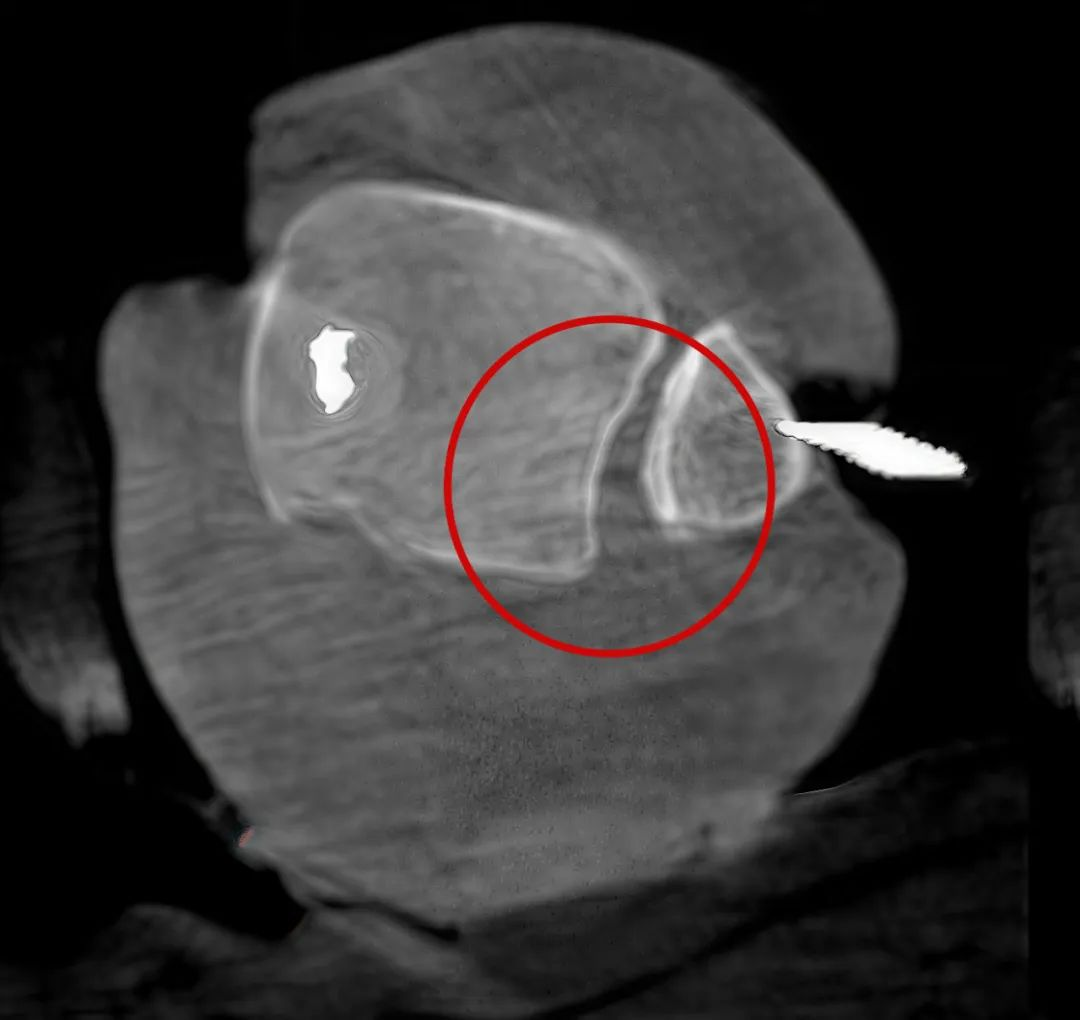

三维切面影像可以看出病灶点

病例3:超声支气管镜下肺活检(80岁)

三维C形臂还可以创新性地应用在呼吸介入领域。例如,在经皮穿刺或经支气管镜肺结节活检、定位、消融等场景中,用于确认工具是否到达病灶、消融范围是否完全覆盖病灶等。

二维影像无法准确判断工具是否到达病灶

三维各切面影像都显示工具达到病灶内